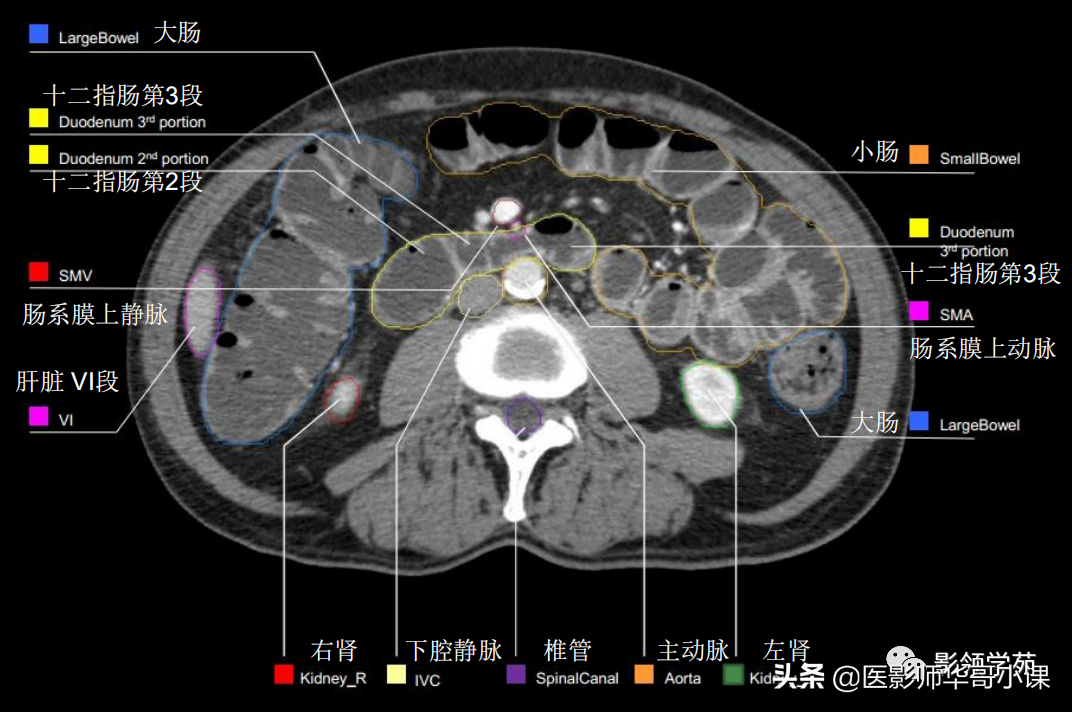

「腹部ct断层解剖」腹部ct扫描横断位解剖 详细标注,值得收藏